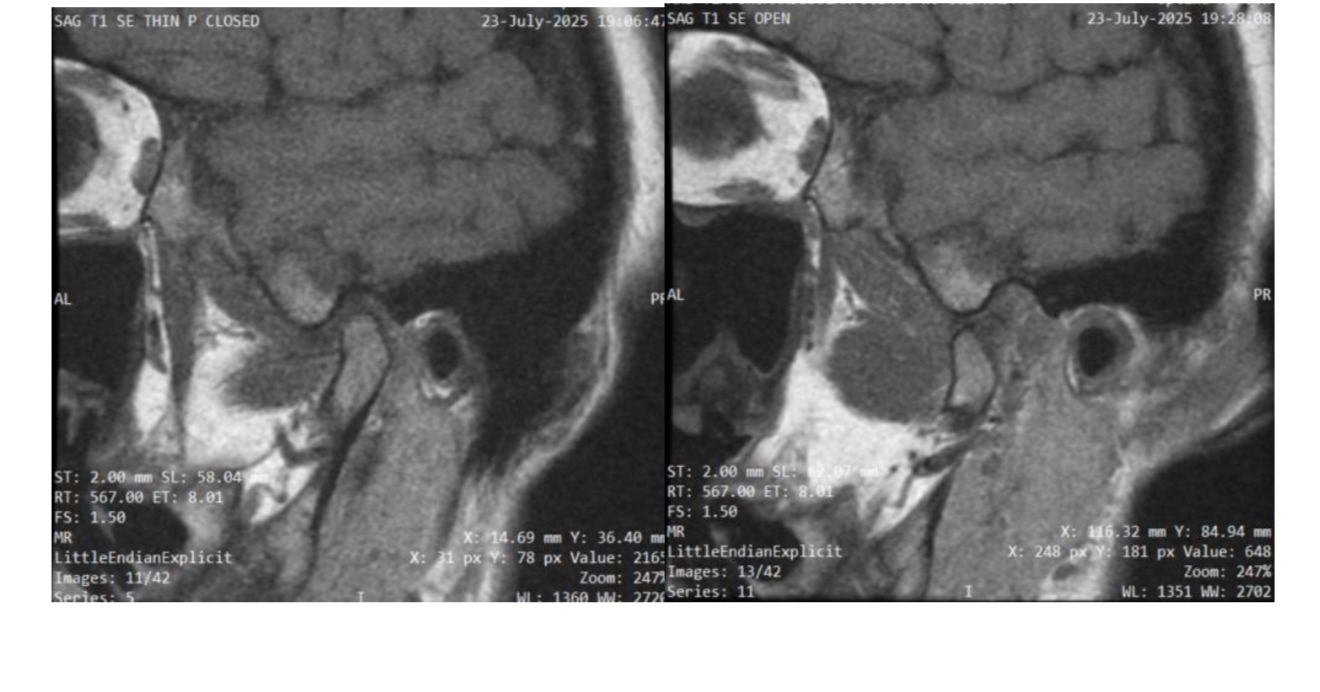

13

Q

What plane

A

Sagittal oblique TMJ (closed vs. open mouth)